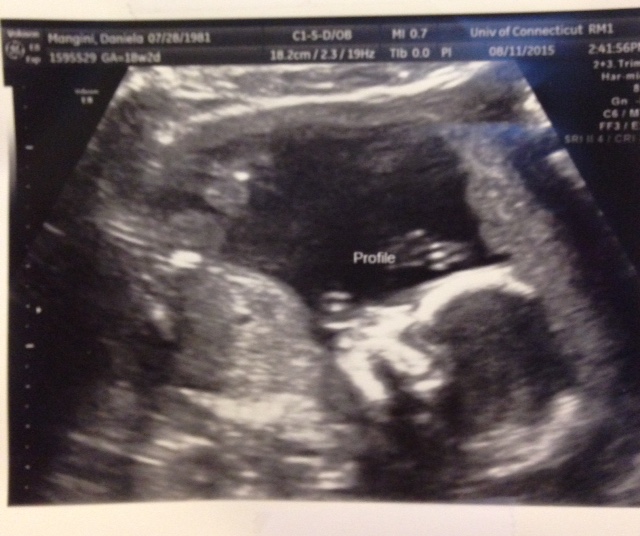

That was the reason I kept this one quiet. I’ve kept it so quiet that I’m very obviously pregnant at 21 weeks and still many people won’t know until I publish this post. I needed it to be that way. I needed to be as alone as I could be with this baby. I had to make myself ready just in case we lost another one. I had to be strong enough to show everyone that I would be okay, not complaining ‘why me’, but being strong in spite of it. And although I am strong, the pain can still be very raw and very real.

Today we pray over this baby daily and anxiously await her arrival in January. We pray she is in perfect health and that she “will not die but live and declare the works of the Lord” (Psalm 118:17). I consider the Shunemmite woman in 2 Kings Chapter 4, that even though she knew her son was dead she ran to the man of God and proclaimed “All is well” and her son came back to life.

On that day in January, when she finally arrives, we will name her Eliana Grace. Eliana means “My God has Answered” and Grace means “God’s favor”. I heard this name in the spring of 2012, not from anyone, it just came into my mind. I actually thought I had created it myself, but I soon learned that wasn’t true. The name had always been there but it’s meaning was for me, in this time and for this child, and it all makes sense now. This baby is God’s answer to the prayers I’ve started years ago and he’s given us His favor…